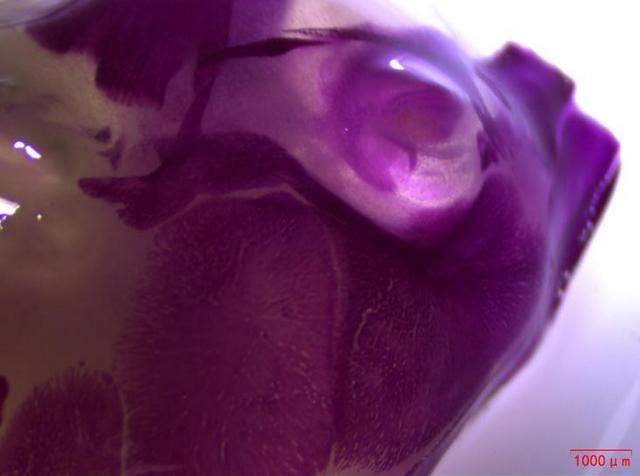

近日,湖南某生物企业引进了Mshot明美生产的体视显微镜MZ101,用于观察小动物大体组织,如小鼠幼崽的脊柱和头部。体视显微镜MZ101以成像清晰、超长工作距离和大视野目镜等显著特点,为生物企业的科研人员提供了良好的观察体验。

在动物实验研究领域,对小动物大体组织的清晰观察至关重要。明美体视显微镜MZ101凭借其高分辨率和优异的光学性能,能够捕捉到小鼠幼崽脊柱和头部的每一个细节,成像效果令人赞叹。这无疑为科研人员提供了准确、可靠的数据支持,有助于推动药物研发进程的顺利进行。